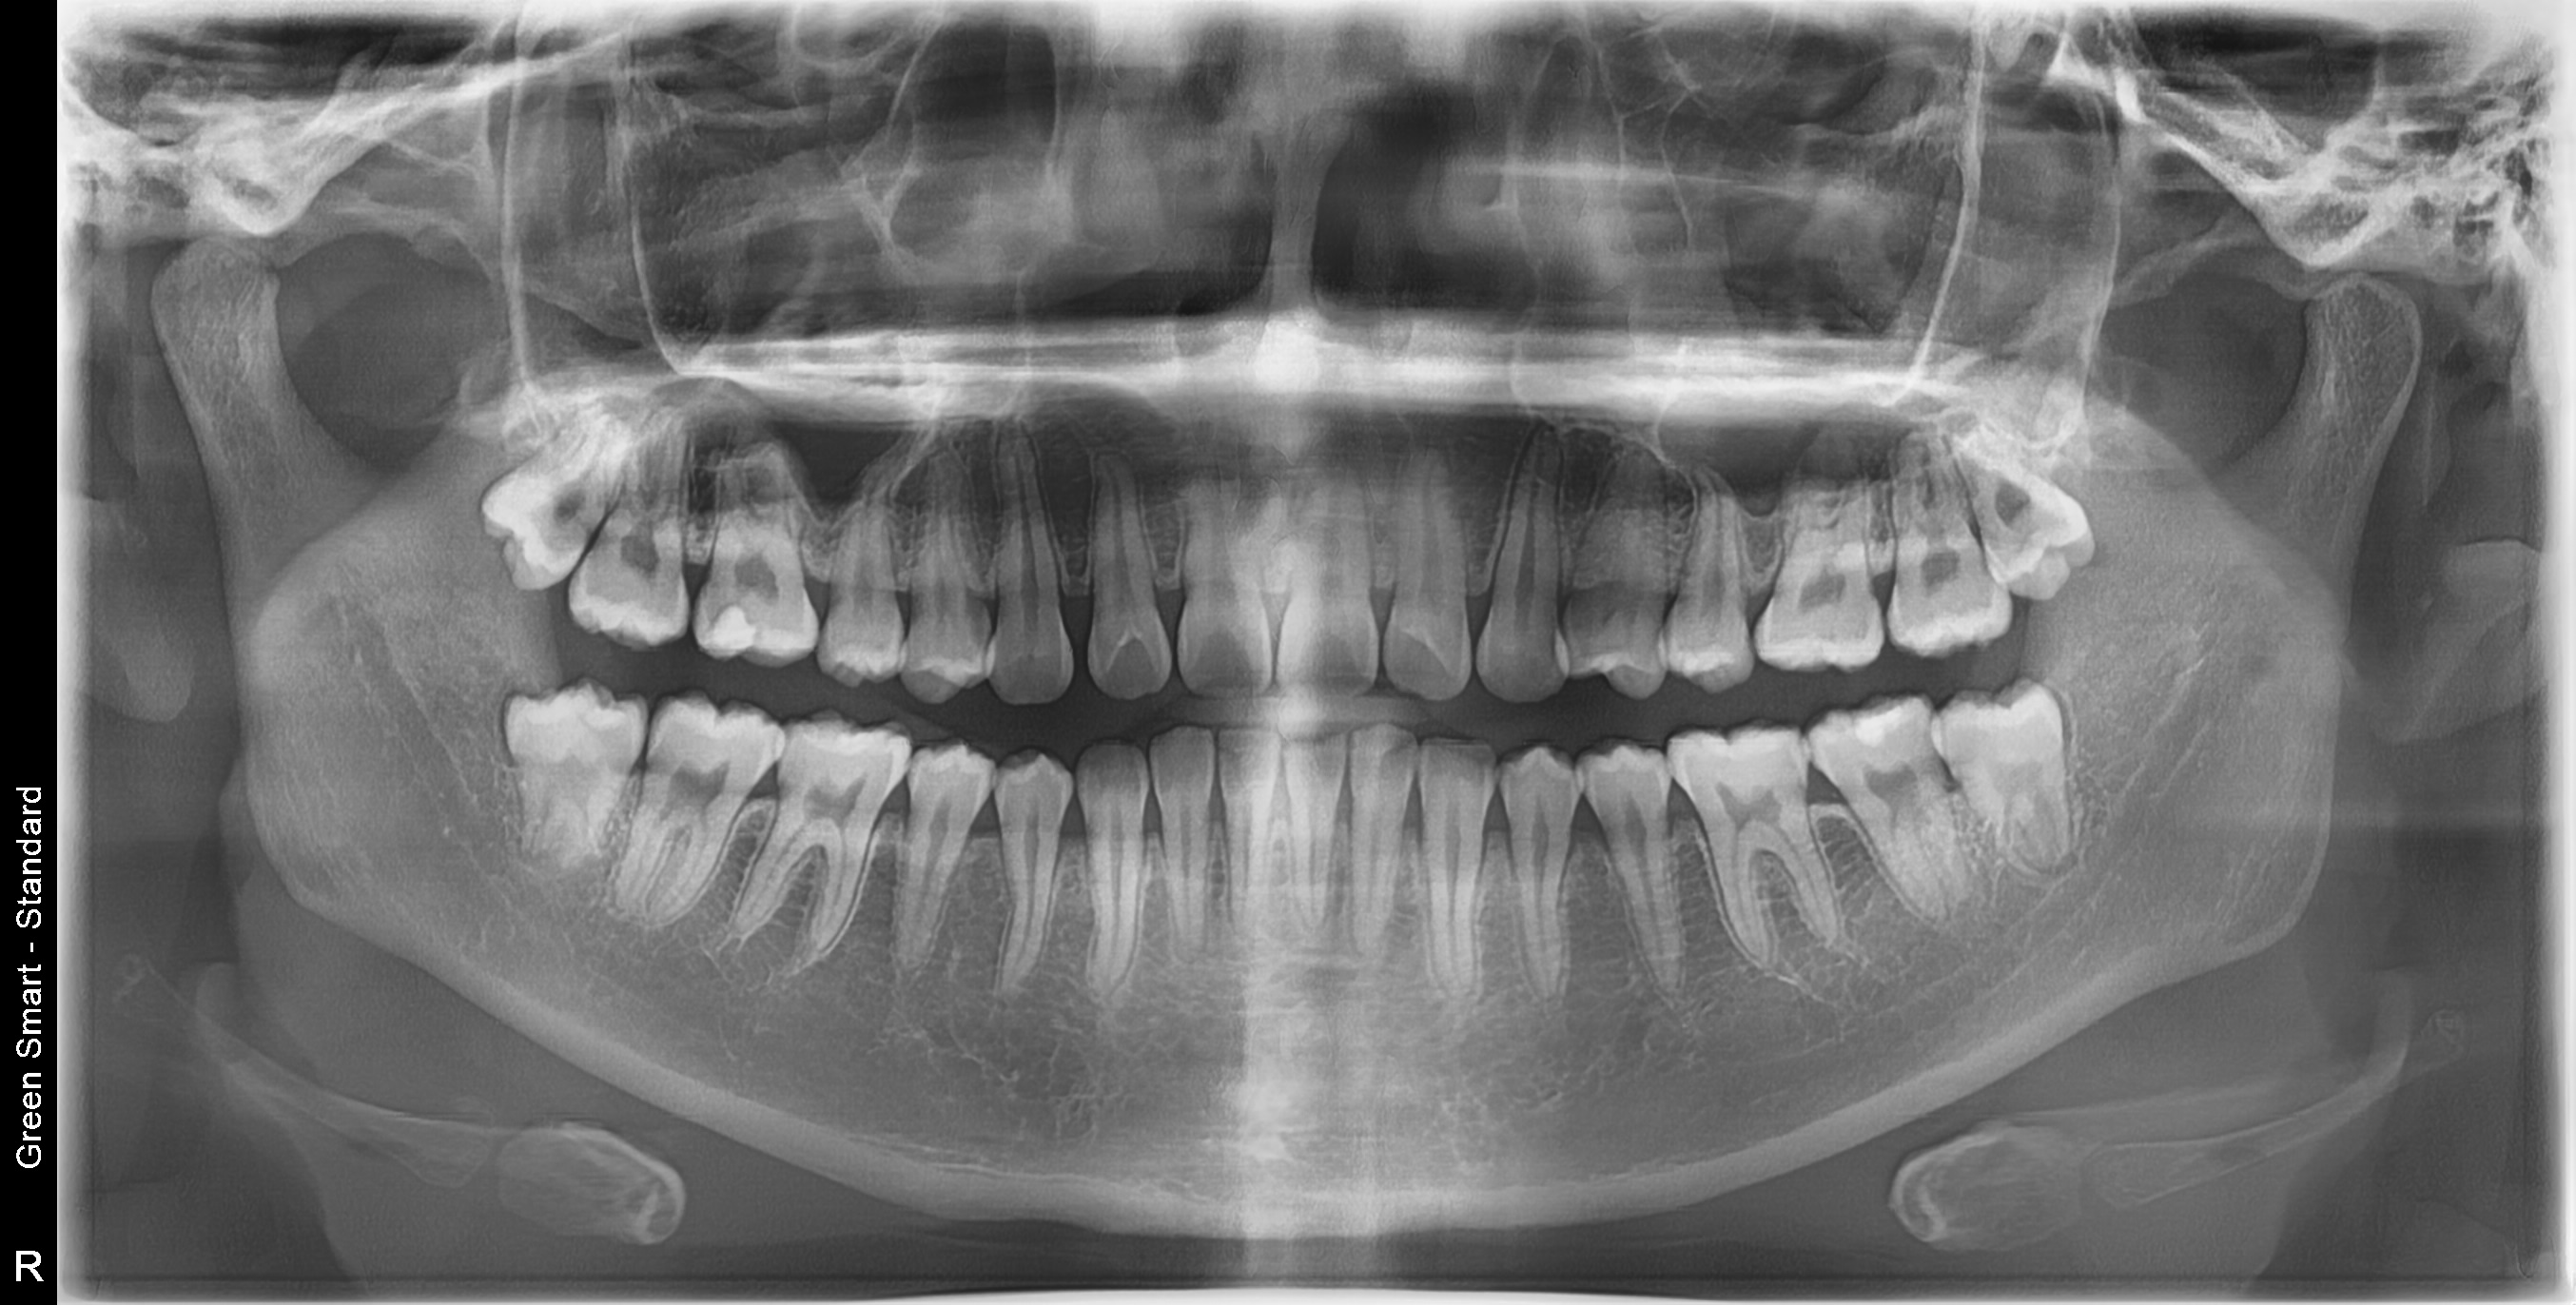

사랑니 상태별 위험도

Before

After

저위험

정상 사랑니

정상적으로 자란 사랑니도 관리가 어려워 충치 위험이 높습니다

중위험

부분매복 사랑니

음식물이 끼기 쉽고 염증이 자주 발생합니다

고위험

완전매복 사랑니

낭종 형성 가능성이 있어 조기 발치가 필요합니다

치근만곡 사랑니

뿌리가 구부러져 있어 발치 난이도가 높습니다

즉시 처치 필요

수평매복 사랑니

앞 치아를 밀어 치열 불균형과 충치를 유발합니다